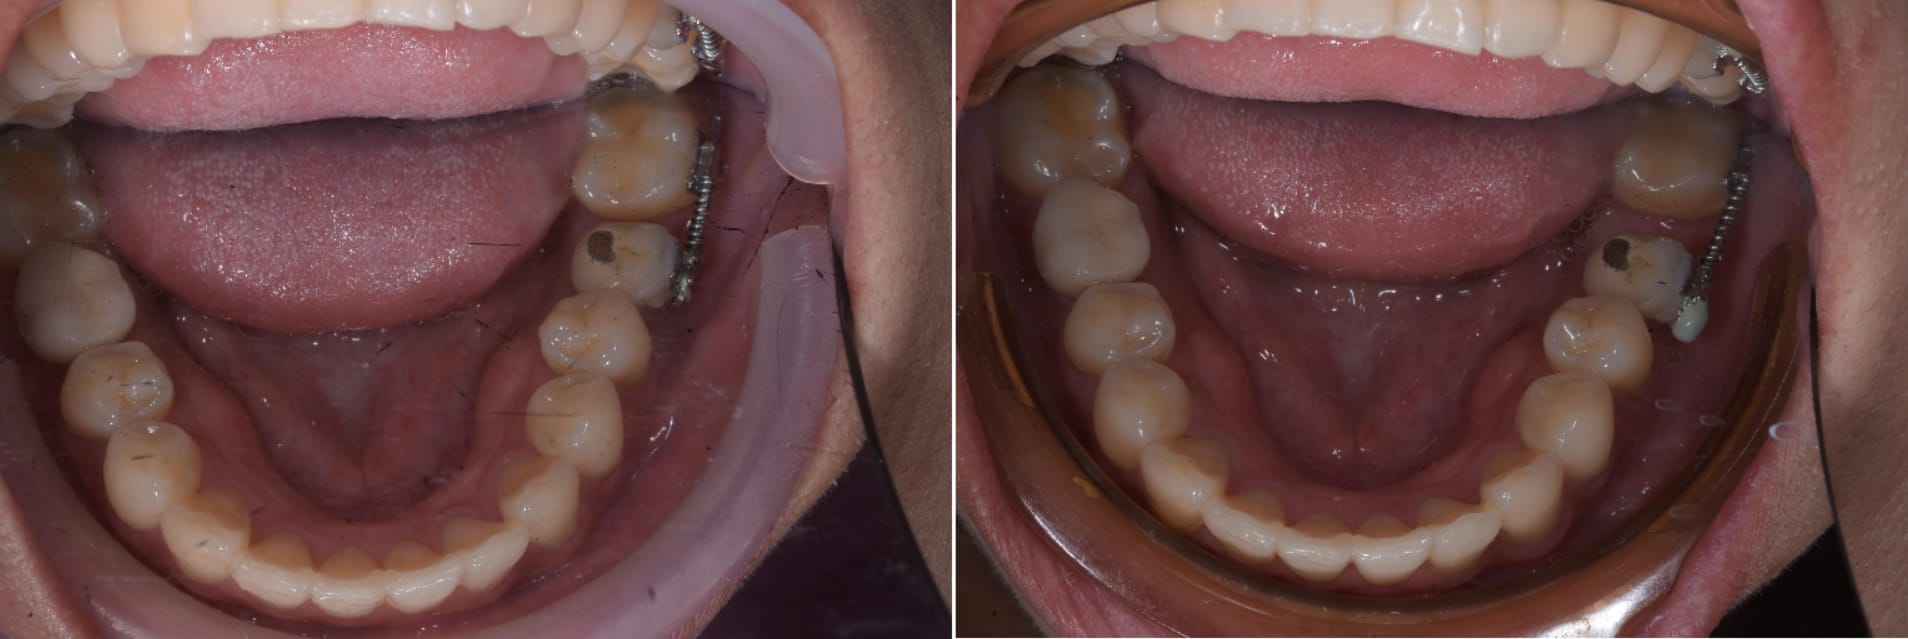

Dans la serie bouger une dent avec un implant, un cas vue ce matin. Deux mois avec un ressort.